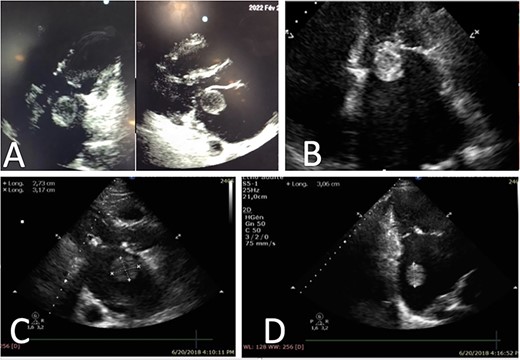

We report the case of a 51-year-old Moroccan female, with history of untreated angina in her early childhood, who presented to the emergency room for stage IV dyspnea and palpitations. On admission, she was diagnosed with acute heart failure and rapid atrial fibrillation (AF) (180 bpm). The echocardiography revealed a very tight MS (mitral valve area: MVA: 0.7 cm2), as well as a dilated LA, with a huge floating thrombus (3 × 3 cm) spinning in the LA causing the intermittent obstruction of the valve (Fig. 1). The patient was urgently prepared for surgery, but unfortunately passed away from cardiac arrest, due to the thrombus closing the valve.

Representative echocardiography images of thrombus ball, (A) TTE views of a thrombus ball blocking the mitral valve (case 1), (B) Apical four chamber view on TTE showing a huge left atrial thrombus ball in contact with mitral valve (case 2), (C) and (D) Left atrial round thrombus on TTE (case 3).

This is the case of a 67-year-old male, with an unknown rheumatic MS. The patient was presented to our unit after aggravating dyspnea along with rapid AF. A transthoracic echocardiography (TTE) was performed, and showed tight MS with commissural fusion (MVA at 0.9 cm2 by planimetry), and a huge ‘ping-pong’ shaped mobile thrombus in the LA (Fig. 1; video 1). No regurgitation was objected. Surgery was indicated and the patient benefited from mitral valve replacement in addition to thrombectomy with success (Fig. 2).

The third patient is a 68-year-old male, who consulted for dyspnea on exertion and palpitations. His physical examination found a mitral diastolic bearing as well as tricuspid regurgitation murmur. The TTE revealed a severe rheumatic MS (MVA: 0.6 cm2) with an important mobile thrombus in the LA (Fig. 1). An important tricuspid regurgitation was also discovered. Emergency cardiovascular surgery was performed, and the patient benefited from mitral valve replacement, tricuspid valvuloplasty and thrombectomy (Fig. 2). The post-operative period was uneventful.